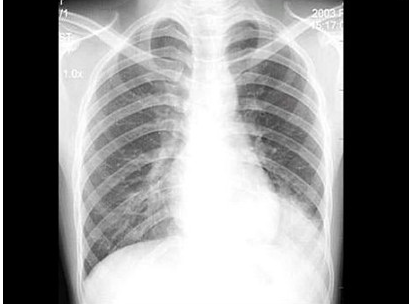

97、单项选择题

男,74岁,咳嗽,咳痰1月余,咯血丝痰1周伴胸痛,胸片如图,最可能的诊断为()

A.右上肺浸润型肺结核

B.右上肺不张

C.右侧中央型肺癌并右上肺不张

D.右侧包裹性积液

E.右肺上沟瘤